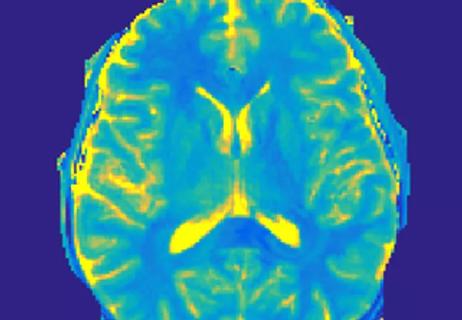

Magnetic Resonance Fingerprinting: A New Window into Multiple Sclerosis

Feasible quantification of MS tissue damage may be at hand